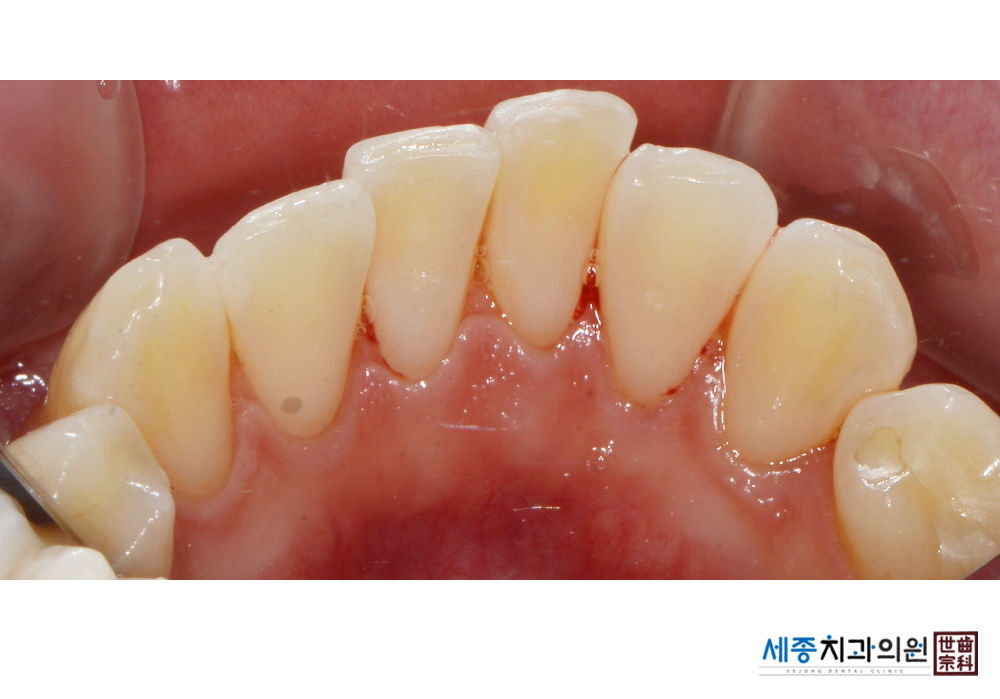

[스케일링] 치주질환 예방 스케일링

치료전 : 2020-01-29

가글마취&저주파 스켈러를 사용한 스케일링